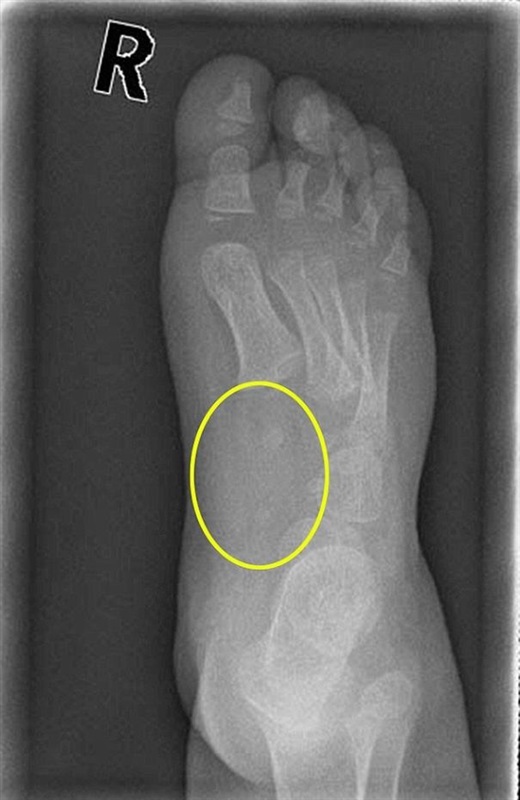

وشخص الأطباء إصابة الطفلة "ليا سودن"، ابنة الـ5 سنوات، بالمرض الغريب عام 2012، بعد أن أظهرت صور الأشعة السينية تفتت أجزاء من عظامها، وقال الأطباء، إن المرض يتسبب بتحور وانتقال خلايا الدم عبر الجسم، ويتسبب بآفات خطيرة أينما حل.

وتابعت والدة "ليا أنجيلا سودن": "عندما قام الأطباء بأخذ خزعة من الورم، اكتشفوا أنه ناتج عن مرض وراثي نادر، وكشفت صور الأشعة الصينية أنه انتشر في جميع خلايا جسدها، وأكل المرض العظام في قدمها، وكانت هناك حفرة عميقة وعظام الناحية اليسرى من الحوض أصغر ومختلفة تماماً عن الناحية اليمنى".